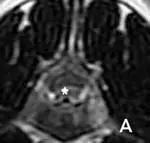

Figure 4 (below). Transverse T2-weighted MRI and soft tissue windowed CT images confirming IVDH in two dogs.(View larger image)

(A) MRI clearly showing ventrally located extruded disk material (*) that is hyperintense relative to the dorsally located, compressed spinal cord. Extruded disk material may appear hyperintense on T2-weighted images when inflammatory infiltrates, hemorrhage, or nonmineralized nuclear materials are present. (B) CT image showing left-sided ventrolateral, extradural compression associated with disk extrusion (arrowhead). Density of the compressing material is consistent with hemorrhage, which can be a significant source of

compression if disk material lacerates the ventral vertebral sinuses.